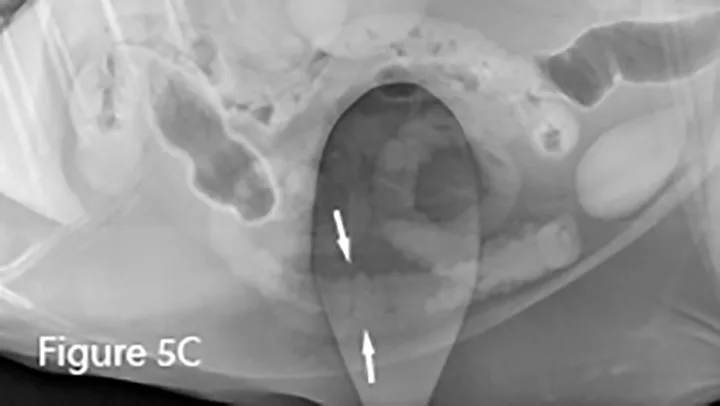

Lateral (Figure 5A) and ventrodorsal (Figure 5B) abdominal radiographs of a cat with string foreign body. Note the plicated (ie, ribbon candy) shape of small intestinal segments, bunched centrally. Pockets of triangular and odd-shaped abnormal intraluminal gas are present, common with linear foreign bodies.

To differentiate normal centralized small intestine from pathologic intestinal bunching, a plastic or wooden spoon may be used to place pressure on the lateral abdomen to disperse the intestinal segments. This cat demonstrated corrugation (ie, undulating serosal margins) of a segment of small intestine, seen in some cases of linear foreign body ingestion causing intestinal plication.

Intestinal plication (arrows) may be seen via ultrasound; in some cases, linear foreign material (arrowheads) may be visible within the small intestinal lumen.